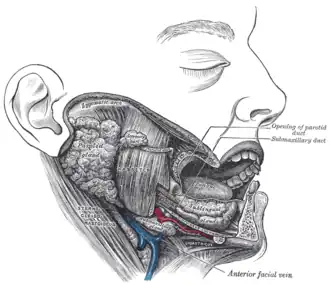

Dissection, showing salivary glands of right side. (Labeled as "submaxillary duct", but is identified as "submandibular duct" in newer sources.) | |

The submandibular duct (also Wharton's duct or historically submaxillary duct) is one of the salivary excretory ducts. It is about 5 cm long, and its wall is much thinner than that of the parotid duct. It drains saliva from each bilateral submandibular gland and sublingual gland to the sublingual caruncle in the floor of the mouth.

Structure

The submandibular duct arises from deep part of submandibular gland, a salivary gland. It begins by numerous branches from the superficial surface of the gland, and runs forward between the mylohyoid, hyoglossus, and genioglossus muscles. It then passes between the sublingual gland and the genioglossus and opens by a narrow opening on the summit of a small papilla (the "sublingual caruncle") at the side of the frenulum of the tongue. It lies superior to lingual and hypoglossal nerves.